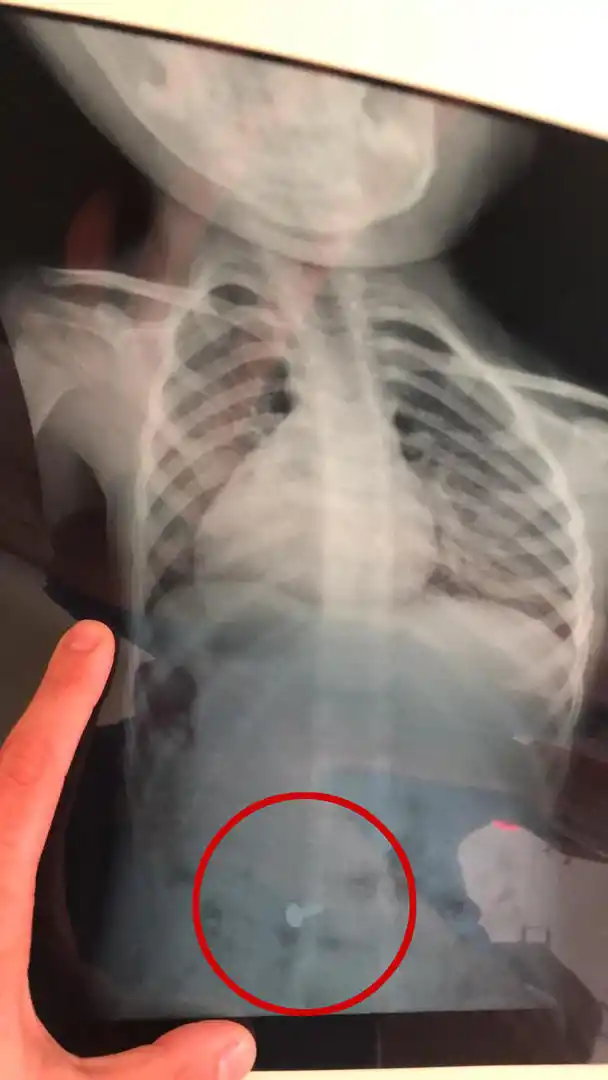

No habían notado nada hasta que Maitena empezó a toser. “¿Qué pasa? ¿Estás bien?”, le preguntó su papá. La pequeña de tres años dijo que sí, y siguió jugando. El padre no se quedó tranquilo. Unos minutos antes había visto que tenía entre sus chucherías una mamadera con tres tornillos adentro. Inmediatamente la buscó y ahí se dio cuenta. Faltaba uno. En la sala de urgencias del Hospital de Niños una radiografía confirmó las sospechas: ahí estaba el objeto de metal; ya había pasado el esófago y estaba ingresando al estómago.

SUSTO. La radiografía de Maitena mostró que se había tragado un tornillo. Por suerte pasó rápido el esófago y luego lo despidió.